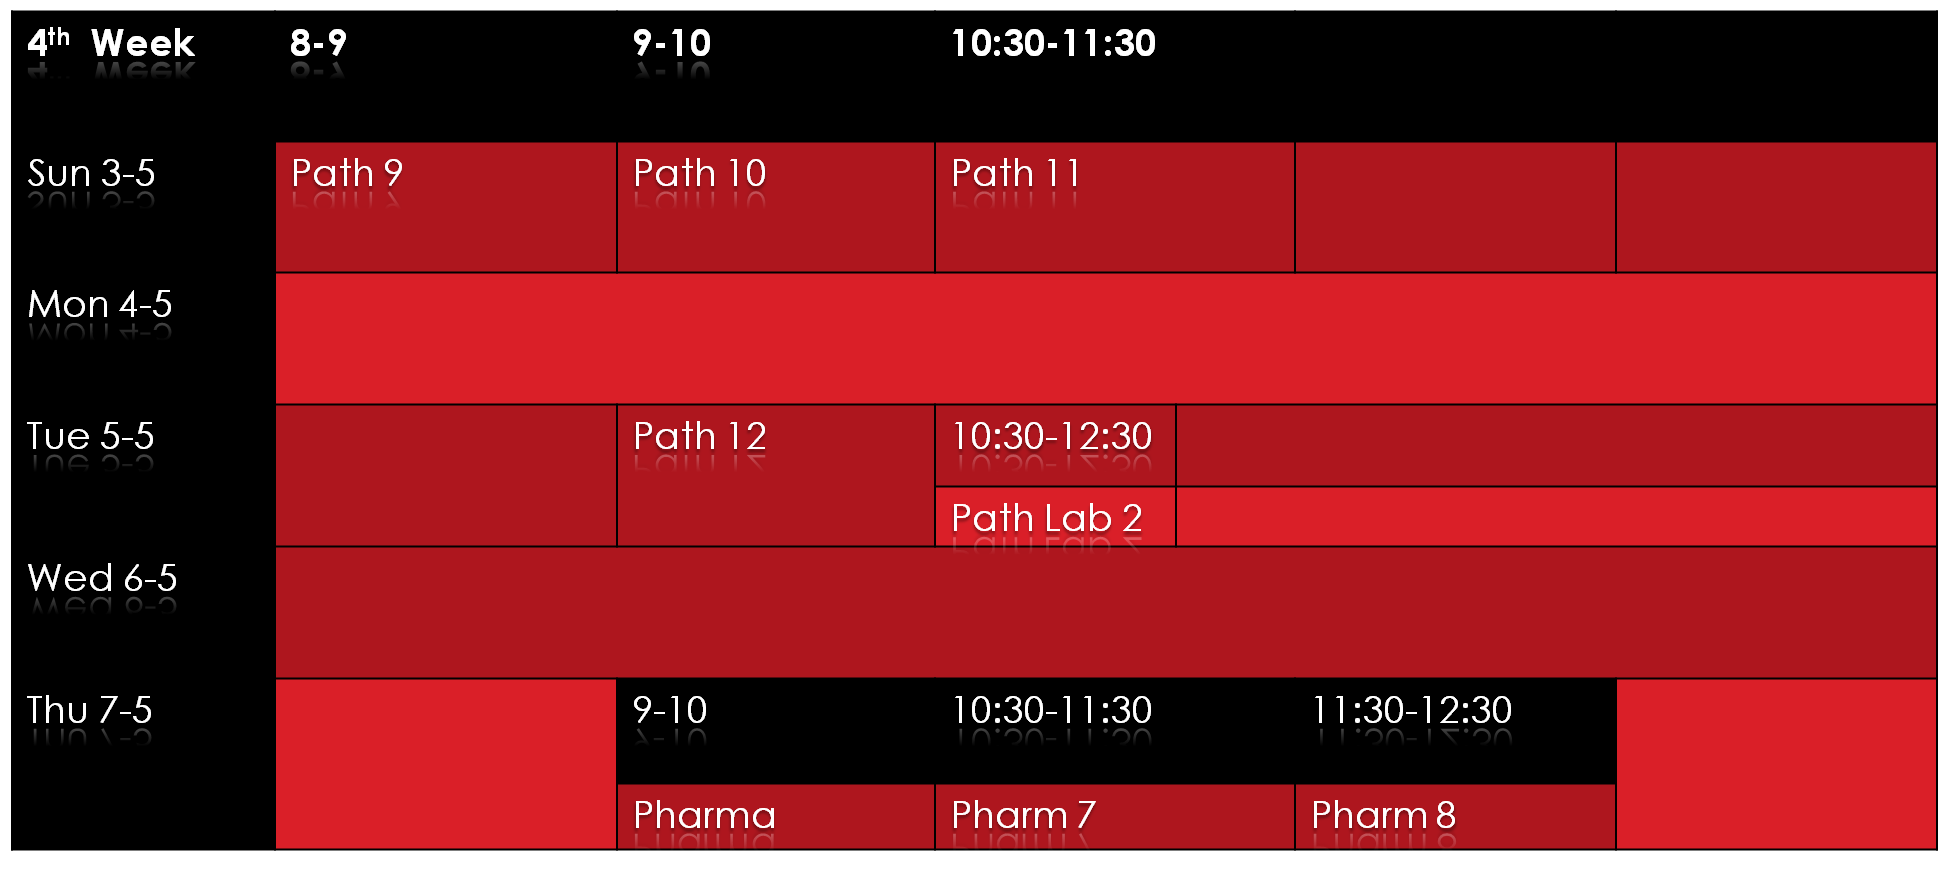

نضع بين ايديكم جدول الاسبوع الثالث و الرابع بعد التعديل ، علماً ان يوم الخميس القادم عطلة رسمية :

[divider line_type=”Small Line” custom_height=””]